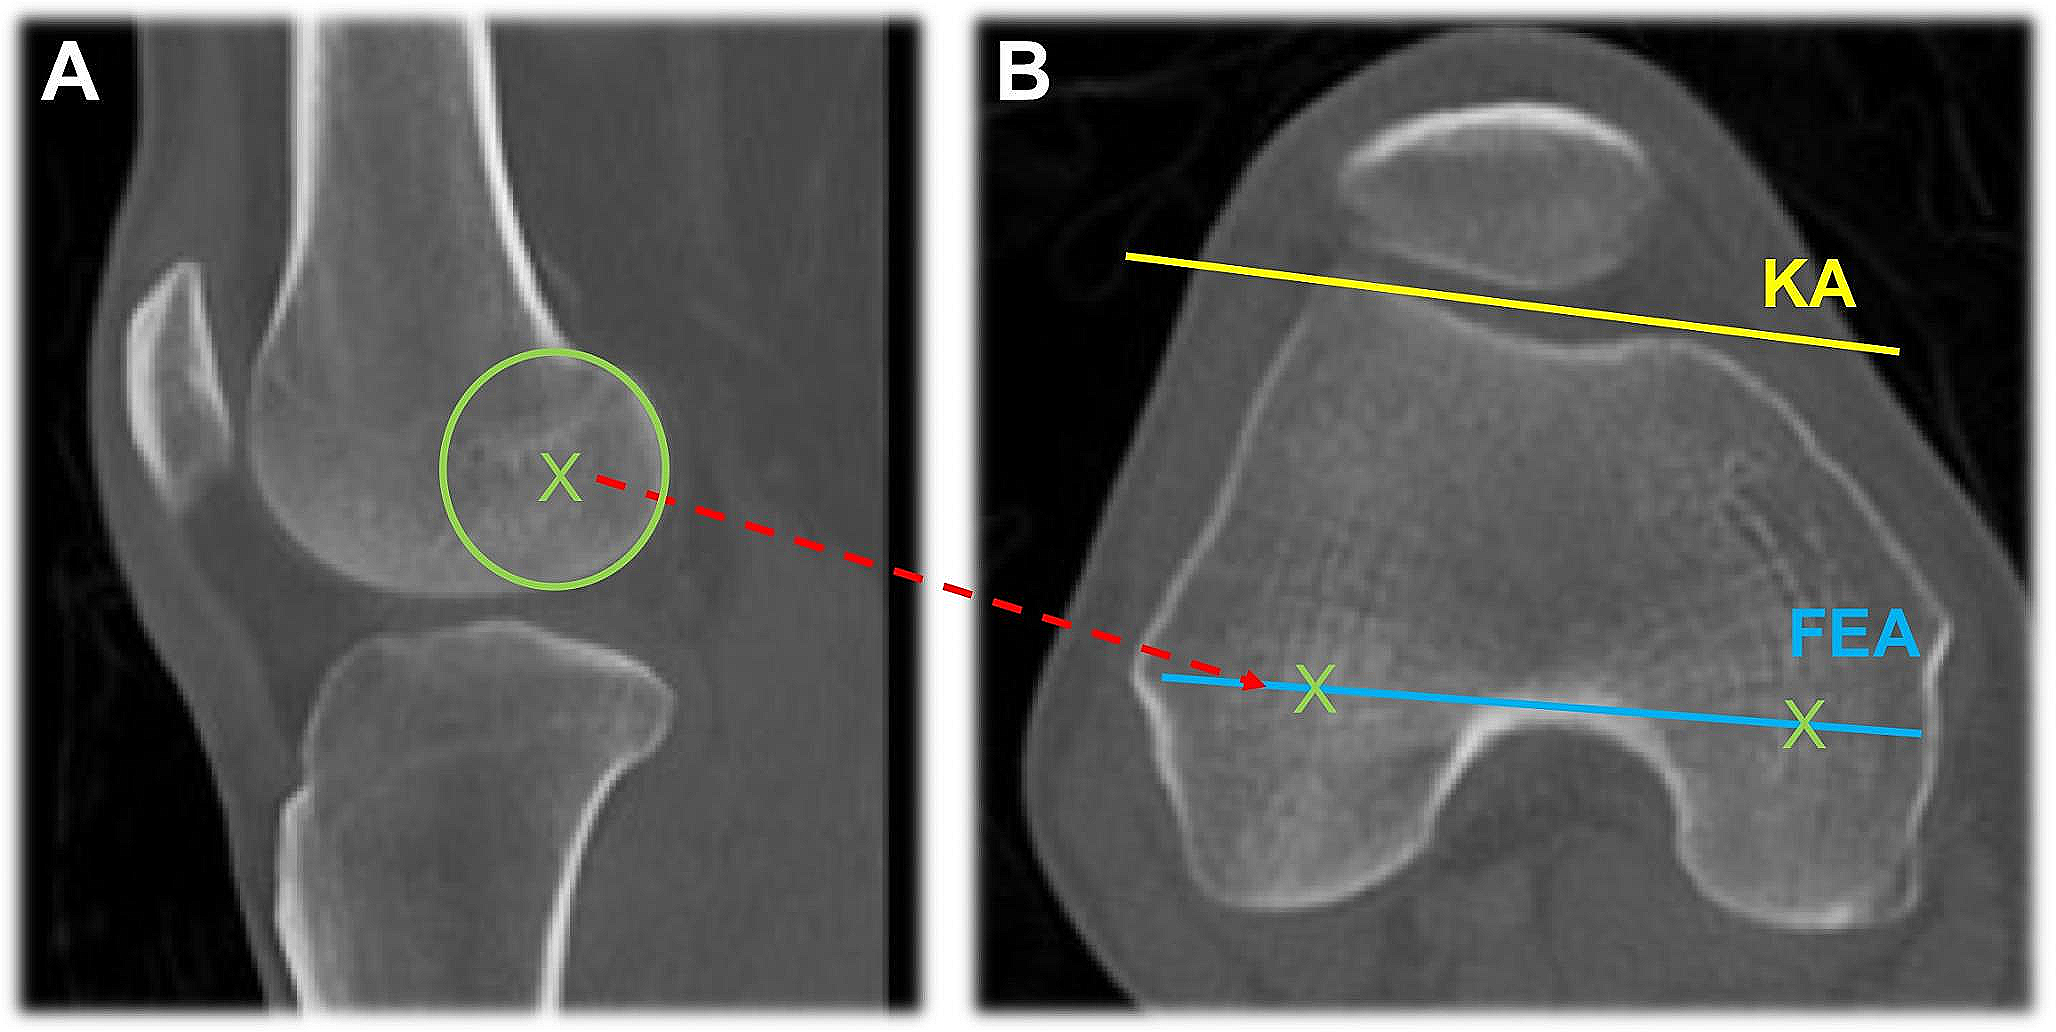

In preoperative CT, FEA was determined by establishing the centers of rotation of the medial and lateral femoral condyle. These parameters were examined in the respective sagittal section plane according to the largest anterior-posterior condyle diameter. Accordingly, the two centers of rotation could be transferred to the axial section plane using a corresponding objective function of the Centricity PACS software. This way the angle to the K-wire axis (KA) could be determined (see Fig. 2). The KA was defined by a Kirschner wire which was inserted in both distal femora. Thus, it could serve as a reference axis of comparability of the pre- and postoperative data.

Fig. 2

CT imaging of the knee. (A) Determination of the posterior centers of rotation marked with green “X” and (B) transfer to the axial section plane. X = posterior centers of rotation, KA = K-wire axis and FEA = flexion-extension axis. Areas refer to the bony structures